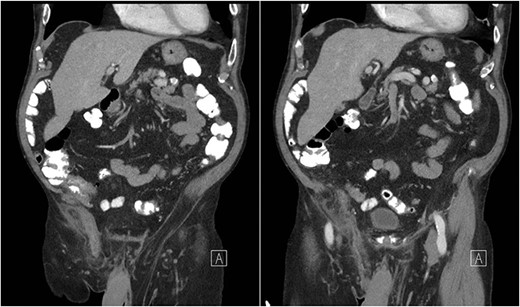

An 81-year-old male with a past medical history of childhood repair of cardiac septal defect presented to our emergency department (ED) with a two-day history of vague abdominal pain that migrated to his right groin with an associated non-reducible right groin mass. The non-reducible groin mass persisted, and his pain progressed that prompted him to come to the ED. Clinical examination revealed a firm, tender and irreducible right inguinal mass. The remaining clinical and laboratory tests were normal. Contrast-enhanced computed tomography (CT) of the abdomen and pelvis was performed. CT presented an acute appendicitis within a right inguinal hernia and a dilated appendix, measuring 13 mm in diameter and demonstrated periappendiceal fat stranding with no evidence of rupture (Figs 1–3). Patients’ history, physical exam and imaging findings were consistent with the preoperative diagnosis of an Amyand’s hernia with acute appendicitis. It was determined the patient will require operative intervention.

Sagittal CT abdomen with oral contrast showing a dilated appendix periappendiceal fat stranding within a right inguinal hernia and no evidence of rupture.